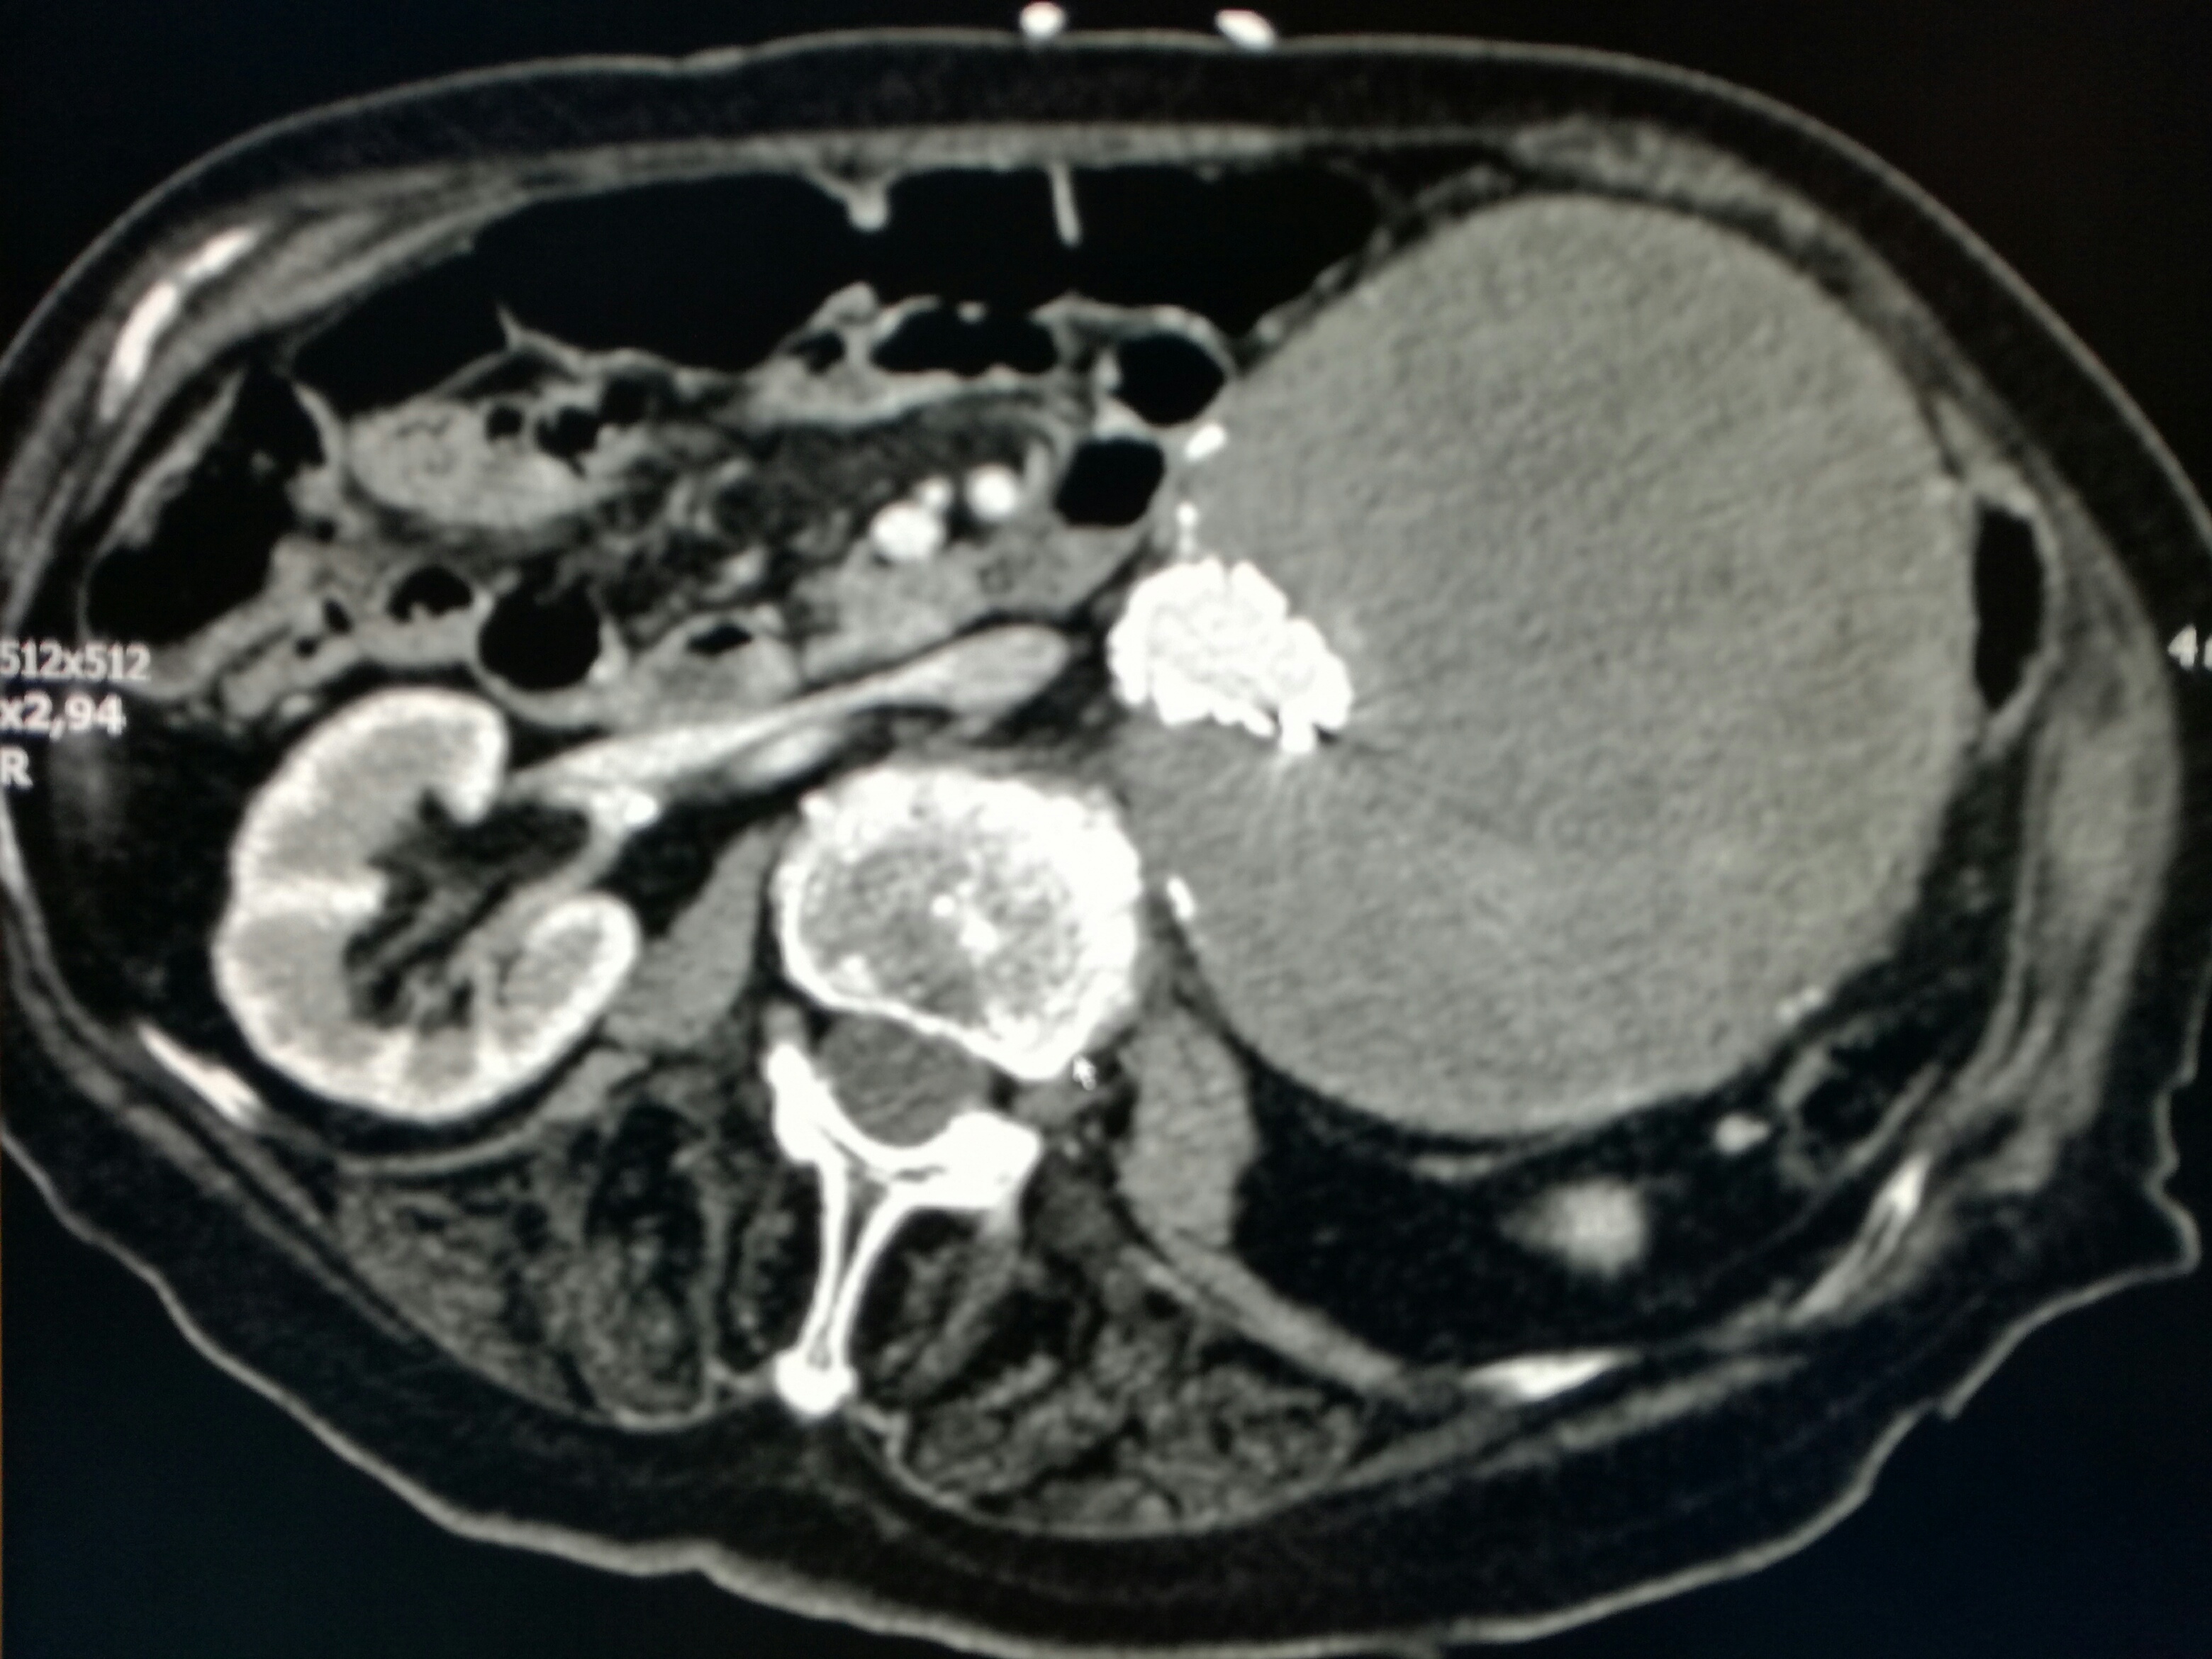

AAA2